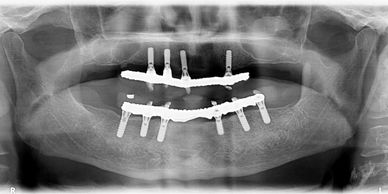

Our All-on-4, All-on-X, pterygoid, and zygomatic implant procedures offer immediate results for patients requiring complete tooth replacement, delivering a fully functional smile in just days.

Our advanced full-arch protocols allow us to extract damaged teeth and place your complete new smile in a single treatment sequence. Most patients leave with their new teeth within 3-5 days of starting treatment.

Using precise angulation and strategic positioning, we maximize available bone structure while minimizing the need for extensive grafting procedures. This approach reduces treatment time and accelerates your return to normal function.